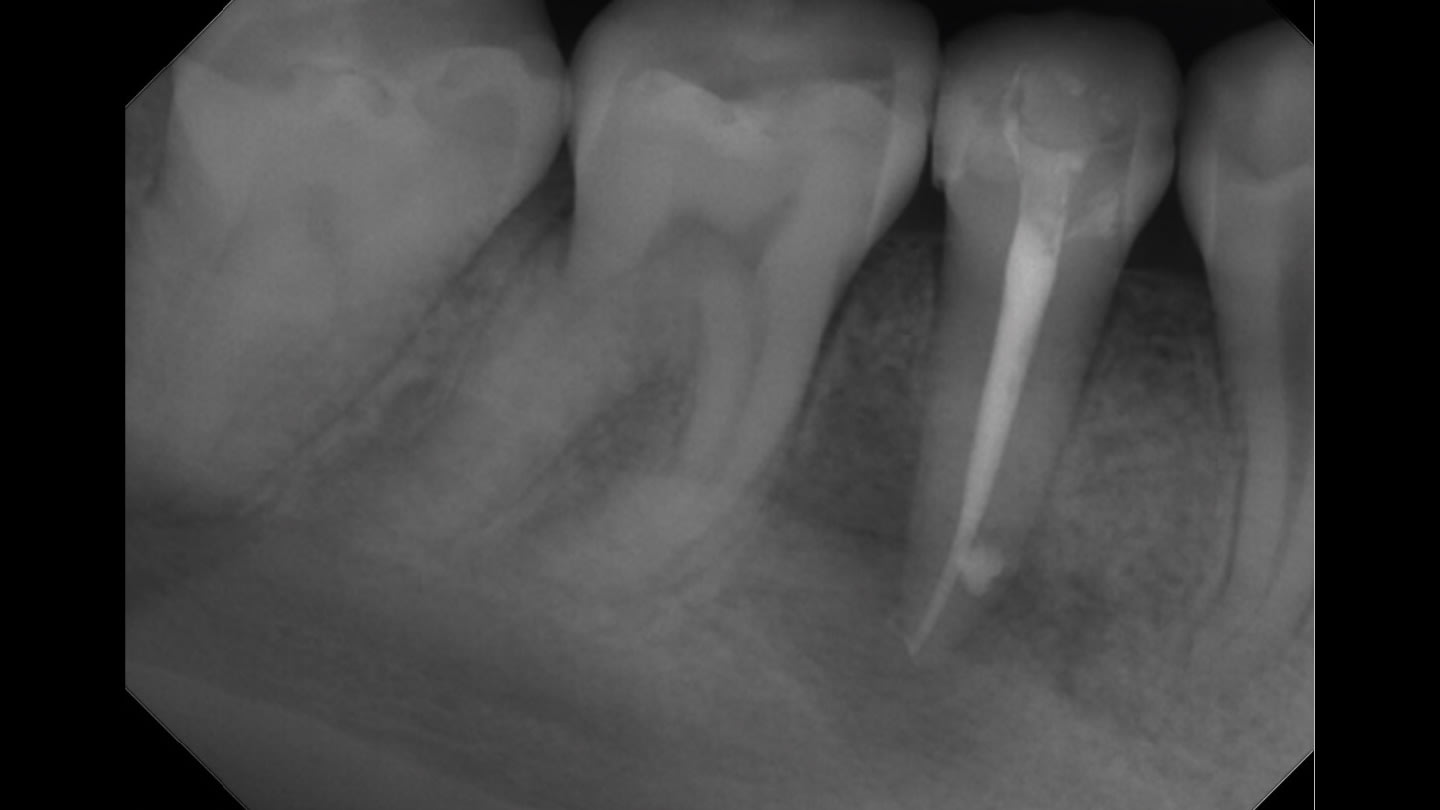

Dr. Kale primarily uses a single-cone obturation technique in single-visit cases, placing the sealer directly into the canal before seating the cone. Because the material forms a thin film and provides adequate working time, he finds that adjustments can be made when necessary without difficulty. “If you need to reposition or remove the cone before the sealer fully sets, it’s manageable,” he says. “That flexibility makes the procedure more predictable.”

Like many clinicians, Dr. Kale views the obturation stage as a critical determinant of long-term treatment success. While irrigation and shaping remove infected tissue and reduce bacterial load, an effective seal is necessary to prevent reinfection of the canal system. “You can perform a beautiful root canal, but if the seal is compromised, bacteria can eventually find their way back in,” he says. The high pH and bioceramic composition of EdgeUtopia Sealer contribute to antimicrobial activity and favorable healing conditions, which Dr. Kale believes can help improve clinical outcomes.

He also emphasizes the importance of maintaining a proper seal during the period between endodontic therapy and placement of the final restoration. In some cases, patients may delay receiving a crown or other definitive restoration, creating the potential for microleakage if the canal system is not adequately sealed. “The material’s low solubility and biocompatibility help provide reassurance that the seal will remain stable during that time,” Dr. Kale says.